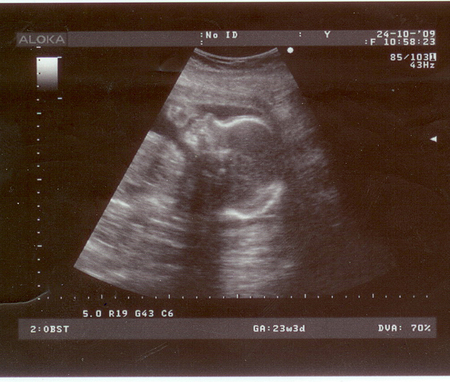

Результаты: УЗИ, КТГ, доплера, скринингаНаконец то я выкладываю фото нашего карапуза))) здесь ему еще 23 недели и видимость не особо. Но все же. Курносик и все дрался кулачками)))